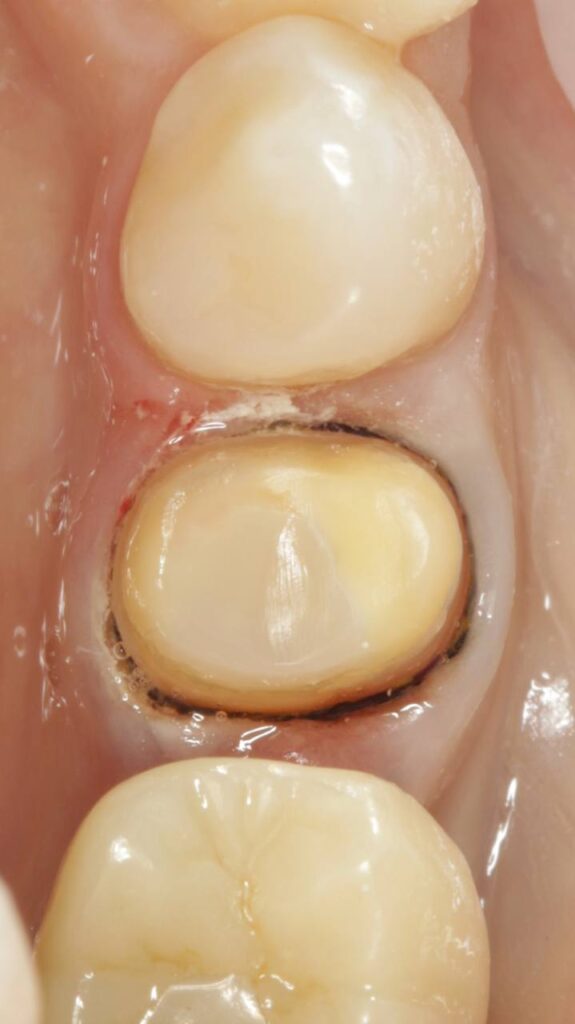

Протезирование коронками из диоксида циркония, после эндодонтического лечения — Исламов Л.А.(01.04.2026)